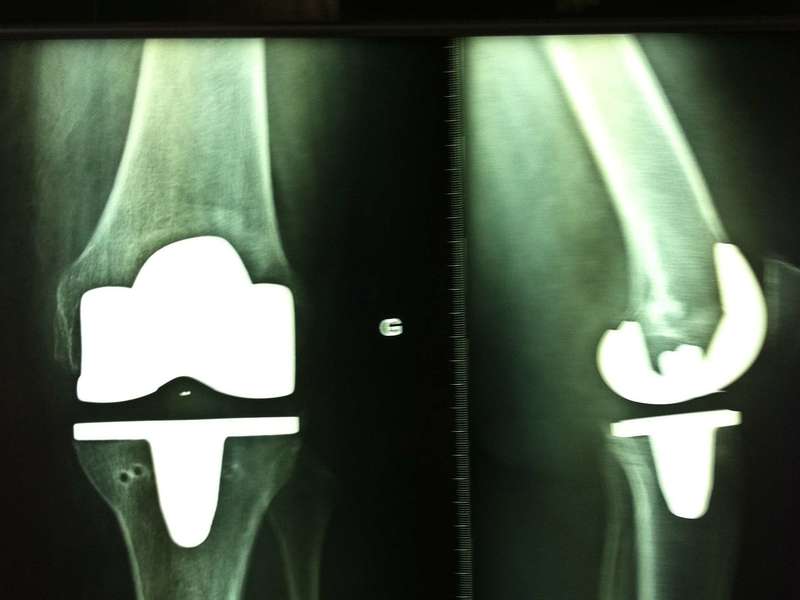

Pour un premier rendez vous, il est préférable de venir avec des examens radiographiques, prescrits par le médecin traitant, en fonction de la pathologie et de l'articulation concernées.